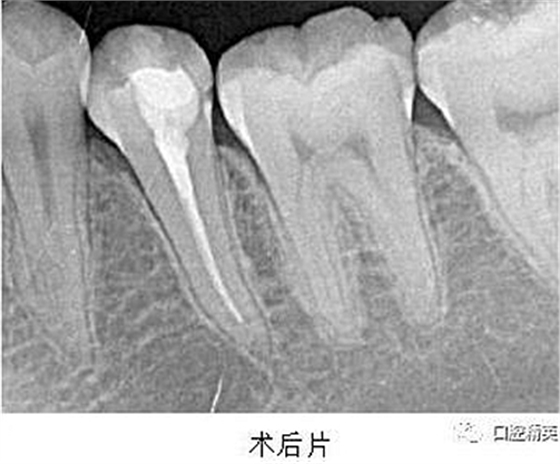

處置:經(jīng)患者及家屬知情同意后,35 局麻,放置橡皮障,去腐,開髓,可見黑色感染物流出,定位根管口,建立直線通路,10# K 銼疏通根管,確定工作長度(19mm),機用鎳鈦器械(M3),次氯酸鈉全程浸泡沖洗,預(yù)備根管至 35 號,0.04 錐度,2ml EDTA 沖洗液緩慢勻速沖洗,超聲蕩洗。試主尖 X-ray 可見恰充,吸潮紙尖拭干根管,導(dǎo)AH-Plus 糊劑,連續(xù)波熱牙膠垂直加壓充填,術(shù)后 X-ray可見根管恰充,SDR 封閉根管口,復(fù)合樹脂充填窩洞,恢復(fù)牙齒形態(tài),調(diào)牙合,拋光。醫(yī)囑

2、扁平根管充填時,應(yīng)該采用混合技術(shù)。因為主牙膠尖往往不適合扁平根管的形態(tài),使得攜熱器很容易將主牙膠尖全部帶出根管?;旌霞夹g(shù)是將連續(xù)波熱牙膠垂直加壓充填法和側(cè)方加壓充填法混合使用,即在插入主尖之后,使用側(cè)方加壓器加壓,追加數(shù)根副尖,直至根尖區(qū)充填致密,繼而使用攜熱器切斷,垂直加壓,熱牙膠回填。

3、根管充填完成之后,要使用流動樹脂或者 SDR 嚴(yán)密封閉根管口,酌情墊底,優(yōu)化洞型,之后再行樹脂充填或嵌體等的修復(fù)。本例建議行嵌體修復(fù),患者由于個人時間問題,希望暫緩修復(fù),于是采用樹脂充填修復(fù)術(shù)。